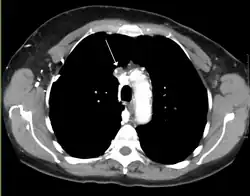

A CT image showing compression of the right hilar structures by cancer

The main techniques of diagnosing SVCS are with chest X-rays (CXR), CT scans, transbronchial needle aspiration at bronchoscopy and mediastinoscopy.[6] CXRs often provide the ability to show mediastinal widening and may show the presenting primary cause of SVCS.[6] However, 16% of people with SVC syndrome have a normal chest X-ray. CT scans should be contrast enhanced and be taken on the neck, chest, lower abdomen, and pelvis.[6] They may also show the underlying cause and the extent to which the disease has progressed.[6]